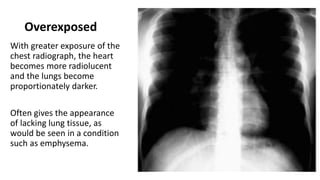

Overexposed

With greater exposure of the

chest radiograph, the heart

becomes more radiolucent

and the lungs become

proportionately darker.

Often gives the appearance

of lacking lung tissue, as

would be seen in a condition

such as emphysema.

Overexposed With greater exposureof the chest radiograph, the heart becomes more radiolucent and the lungs become proportionately darker. Often gives the appearance of lacking lung tissue, as would be seen in a condition such as emphysema.

• 12.